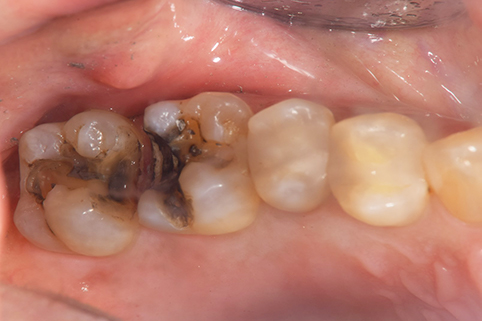

インレー症例

治療前

途中経過

治療後

年齢・性別 43代・女性

主訴 パラジウムインレー2次カリエスの治療

治療内容 左上6セラミックインレー・

左上7ゴールドインレー

治療期間 10日程度

リスク・副作用 虫歯が深ければ、つけた後しみたり、痛みが出る可能性がある。 その場合は神経をとる処置をする。

歯ぎしり、くいしばりでセラミックインレーが割れることがある。

費用 セラミックインレー 55,000円

ゴールドインレー 88,000円